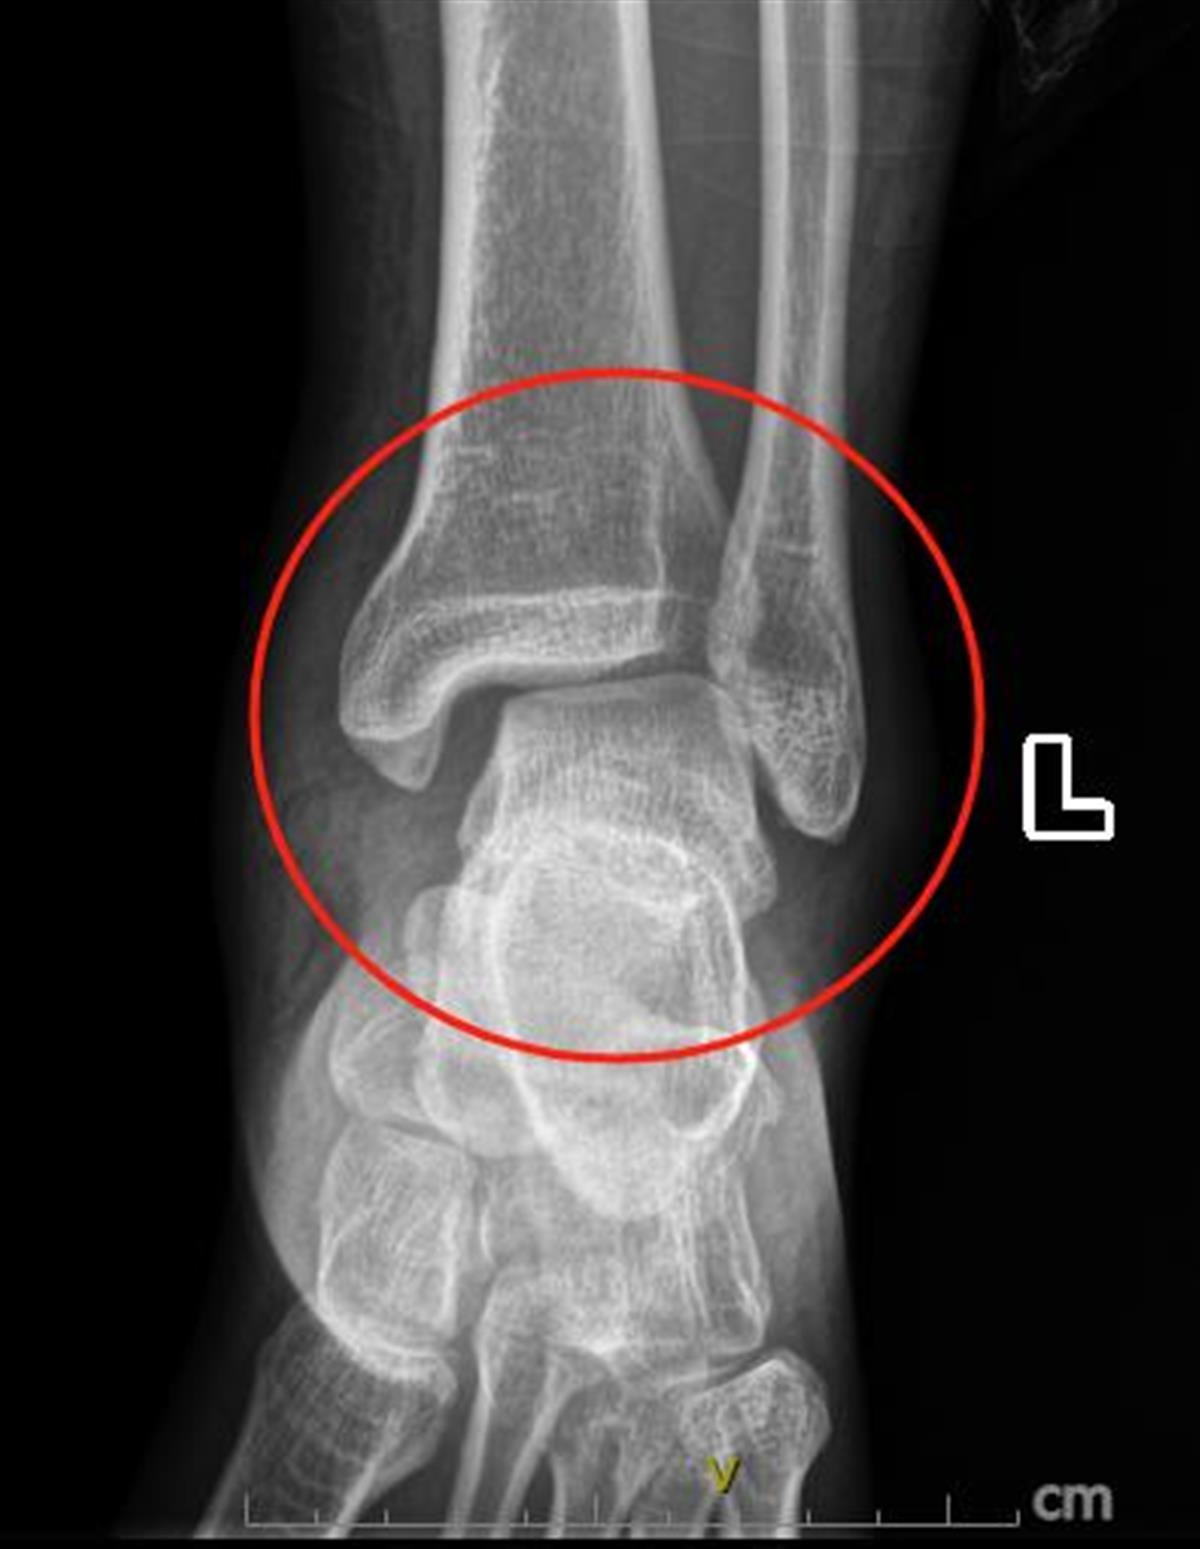

创伤骨科/足踝外科专家团队经过进一步检查,发现孔先生系Maisonneuve损伤,即踝关节脱位、腓骨上段骨折、下胫腓分离。这种损伤十分少见,非常容易漏诊,一旦孔先生选择了打完石膏回家观察的保守治疗,将会导致他的左足畸形愈合,行走功能障碍,创伤性关节炎,慢性踝关节疼痛,踝关节不稳定,甚至可能会导致下肢关节的对位对线不良,人体力线不正常,进而影响到全身的关节和肌肉系统,严重的更是会造成终身跛行与残疾。

术前可见孔先生踝关节韧带损伤撕裂

“一般医生往往会关注踝关节疼痛,从而忽视了小腿近端的疼痛,而在影像学检查的时候,不会刻意去关注腓骨近端的影像,从而忽视了Maisonneuve损伤。”创伤骨科主治医师周旺表示,孔先生的病症主要是在踝关节旋转时受到暴力,从而导致踝关节内踝或者后踝的骨折,另外暴力会向上传导,传导至腓骨近端,使腓骨近端也产生骨折。由于其涉及下胫腓韧带及胫腓骨骨间膜,这个骨折是在受暴力的情况下损伤的,损伤比较重,需要手术治疗。”